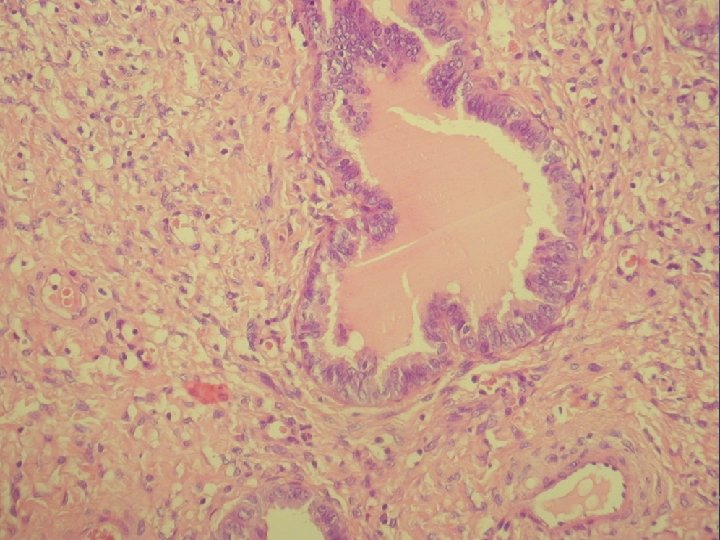

prolaps tuby asociovaný s exuberantnou angiomyofibroblastickou strómou

Klinicky: chronická abdominálna bolesť, dyspareunia polypoidné hemoragické masy Ø Histologicky: prezencia tubálneho epitelu s

Klinicky: chronická abdominálna bolesť, dyspareunia polypoidné hemoragické masy Ø Histologicky: prezencia tubálneho epitelu s variabilnou architektonikou v edematóznej, prevažne fibrotickej stróme Ø glandulárne prevažne tubálne inklúzie z malých epiteloidných buniek s eozinofilnou cytoplazmou, s riasinkami, sekretorické a „peg“ cells

Ø hladkosvalové vlákna a lymfoplazmocytárny infiltrát Ø bohatá vaskularizácia v retiformnej stróme, miestami aj

Ø hladkosvalové vlákna a lymfoplazmocytárny infiltrát Ø bohatá vaskularizácia v retiformnej stróme, miestami aj myxoidnej Ø Imuno: silná desmin pozit. Ø CD 34, S-100, alfa aktin, CK, calponin negat. Ø prezentovaná reaktívna stromálna proliferácia publikovaná v dvoch „case reportoch“